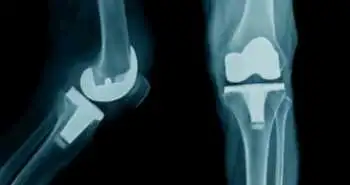

Уровень экспрессии CD64 на нейтрофилах в синовиальной жидкости: скрининговый биомаркер перипротезной инфекции сустава

Перипротезная инфекция сустава является одной из основных клинических проблем. Уровень экспрессии CD64 (Fc-гамма-рецептора 1, FcγR1) на нейтрофилах играет важную роль в регулировании воспаления при бактериальной инфекции, а значит, может быть ценным биомаркером перипротезной инфекции сустава. Цель данного проспективного исследования состояла в оценке диагностических возможностей теста на определение уровня экспрессии CD64 в синовиальной жидкости и крови по сравнению со стандартными клиническими исследованиями, которые позволяют отличить перипротезную инфекцию сустава от асептической несостоятельности имплантата.

В исследование были включены 50 пациентов, которым была проведена ревизия эндопротеза тазобедренного и коленного суставов. По результатам оценки с использованием критериев Общества скелетно-мышечных инфекций (MSIS) 25 пациентов были определены в группу наличия инфекции и 25 пациентов в группу отсутствия инфекции. Перед проведением вмешательства у всех пациентов определяли уровень экспрессии CD64 на нейтрофилах и долю полиморфоядерных нейтрофилов (PMN, %) в синовиальной жидкости, уровень С-реактивного белка в сыворотке крови, уровень экспрессии CD64 и СОЭ в сыворотке крови. Для каждого биомаркера осуществляли анализ площади под кривой зависимости концентрации от времени (AUC) и кривых операционных характеристик приемника (ROC-кривые).

Статистически значимых различий по показателям уровня экспрессии CD64 в сыворотке крови между группами не выявлено. Различия уровня экспрессии CD64 и доли полиморфоядерных нейтрофилов в синовиальной жидкости обеспечили хорошую дифференциацию между группой перипротезной инфекции сустава и группой асептической несостоятельности, при этом AUC равнялась 0,946 и 0,938 независимо друг от друга. Оптимальное пороговое значение уровня экспрессии CD64 в синовиальной жидкости для анализа на перипротезную инфекцию составило 0,85, при этом чувствительность анализа = 92,00 %, специфичность = 96,00 %, а диагностическое отношение шансов (ДОШ) = 227,11.

Таким образом, можно сделать вывод, что при проведении скрининга на перипротезную инфекцию уровень экспрессии CD64 в синовиальной жидкости может служить эффективным лабораторным маркером.